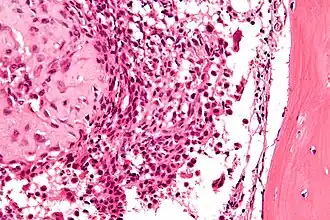

| Micrografia de um condroblastoma com H&E. | |

Pode ser localizado e medido com uma radiografia(RX), tomografia computadorizada (TC), ressonância magnética (MRI) ou cintilografia óssea, mas necessita uma biópsia para ser diferenciada de outros tumores ósseos. Exibem cartilagem imatura, células gigantes e edema medular assim como um fibroma condromixoide, mas geralmente podem ser diferenciados por sua localização. [3]